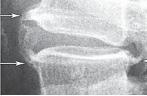

Рассмотрим серию снимков.

Рентгенограмма № 4